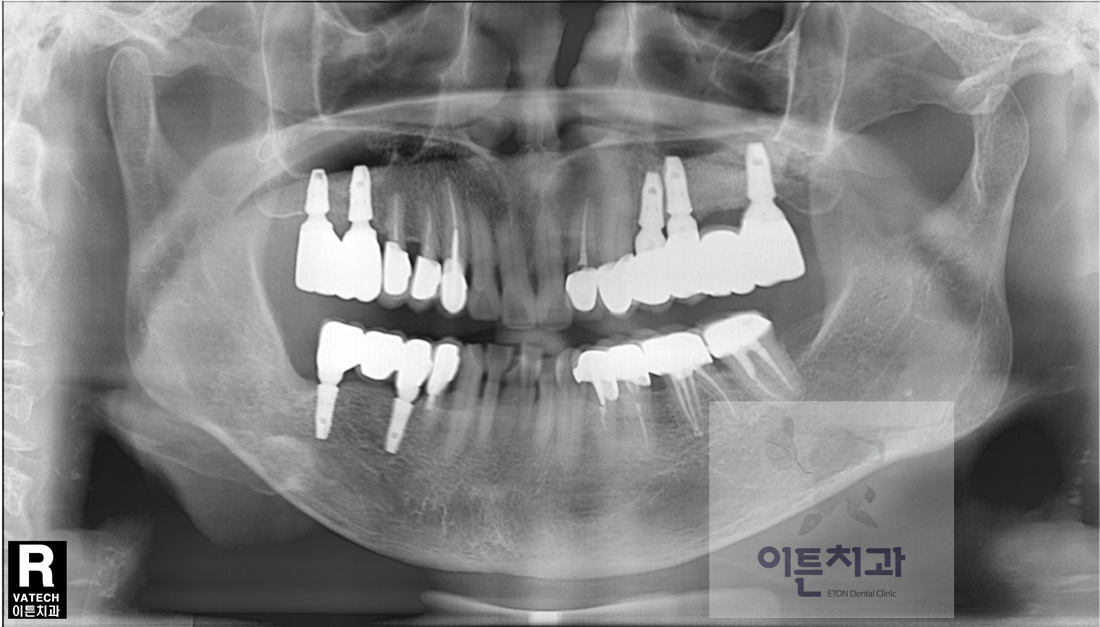

´Ù¼öÄ¡¾Æ ÃæÄ¡ Ä¡·á, ±Ù°üÄ¡·á ¹× »ó¾Çµ¿ °ñ À̽ļú, Ä¡Á¶Á¦ Áõ°¼ú µ¿¹Ý ÀÓÇöõÆ® ¼öº¹ Áõ·Ê

¿À·§µ¿¾È ÁÂÃø À§ ¾î±Ý´Ï°¡ ¾ø¾î ¿ìÃøÀ¸·Î¸¸ ÀúÀÛÇØ¿À¼Ì´ø 60´ë ¿©¼º ȯÀÚºÐÀ̽ʴϴÙ.

¿ìÃø¿¡´Â ¿À·¡Àü¿¡ Ä¡·á¹ÞÀº Ä¡¾Æµé¿¡ ´Ù½Ã ÃæÄ¡°¡ »ý±ä »óȲÀ̾ú½À´Ï´Ù.

¿ìÃøÀÇ ¿À·¡µÈ º¸Ã¶¹°À» Á¦°ÅÇÏ¿© ±× Áß Ä¡·á ºÒ°¡´ÉÇÒ¸¸Å ¼Õ»óÀÌ ½ÉÇÑ Ä¡¾ÆµéÀº ¹ßÄ¡ÇÑ ÈÄ ÀÓÇöõÆ®·Î ¼öº¹Çϰí Ä¡·á °¡´ÉÇÑ Ä¡¾ÆµéÀº ÀûÀýÇÑ Ä¡·á ÈÄ ´Ù½Ã º¸Ã¶ ¼öº¹ÇÏ¿´½À´Ï´Ù.

ÁÂÃø À§ ¾î±Ý´Ï ºÎÀ§´Â ÀÓÇöõÆ® ¼öº¹Çϱ⿡ ³²¾ÆÀÖ´Â Ä¡Á¶°ñ·®ÀÌ ¼öÁ÷, ¼öÆòÀûÀ¸·Î ¸Å¿ì ºÎÁ·ÇÏ¿© µÎ ´Ü°è·Î ³ª´©¾î Ä¡·áÇÏ¿´½À´Ï´Ù.

¸ÕÀú °ñÀ̽ÄÀ» ÇÏ¿© Ä¡Á¶°ñÀ» Àç°ÇÇϰí, ±× ÈÄ Àç°ÇµÈ Ä¡Á¶°ñ¿¡ ÀÓÇöõÆ®¸¦ ½Ä¸³ÇÏ´Â °ÍÀÔ´Ï´Ù.

ÃÑ 8°³¿ù Á¤µµÀÇ Ä¡·á±â°£ÀÌ ¼Ò¿äµÇ¾úÀ¸¸ç, ÁÁÀº °á°ú¸¦ ¾òÀ» ¼ö ÀÖ¾ú½À´Ï´Ù.